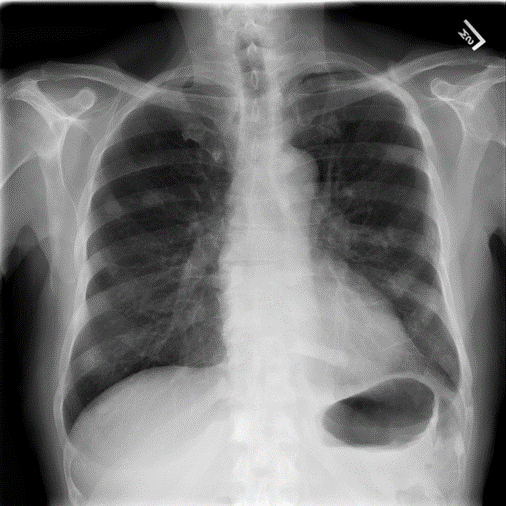

Refer to caption

Figure 9: Typical CXRs with pneumonia-like lung opacity from among the top 1,000 CXRs most likely to have an abnormality according to the logarithm posterior probability out of the 13,863 abnormal CXRs. The lesion is indicated with a red arrow if applicable.

Figure 9 shows CXRs suggested to have pneumonia-like lung opacity with the logarithm posterior probability. These CXRs are the top 1,000 CXRs most likely to have an abnormality out of the 13,863 abnormal CXRs.